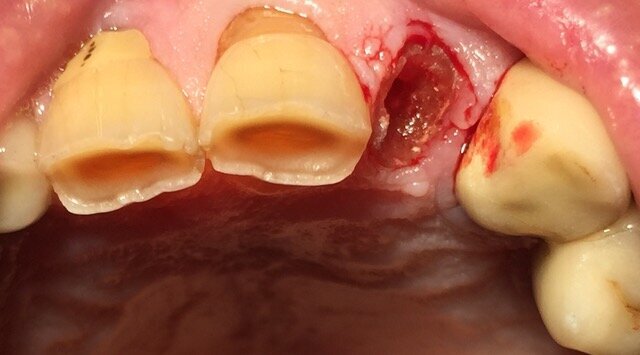

Le foto esplicative si riferiscono a un caso di riabilitazione estetica su paziente maschio di anni 76 con storia di bruxismo, in cui è stato inserito con carico immediato un impianto post estrattivo su 2.2 con mantenimento parziale del tavolato vestibolare nel rispetto del concetto di tunnel protesico di inserzione (Fig. 1). Il collare in zirconia è stato inserito per 1 mm sotto il tavolato e la porzione emergente ha la funzione di mantenimento a balcone del bombè connettivale e quindi di sostegno per i tessuti molli (Figg. 2, 3). La protesizzazione, avvenuta nelle 72 ore successive all’inserimento della fixture, è stata effettuata con impronta pick up e tecnica cementata con corona in PMMA eseguita al cad cam; l’angolo incisale della corona risultava assai smusso distalmente per agevolare i movimenti di svincolo in lateralità poiché il paziente è bruxista, come si evince dalle faccette di usura degli elementi naturali adiacenti (Fig. 4). Nonostante il biotipo gengivale sottile già nelle prime fasi dal carico si può notare l’effetto biomimetico del collare in zirconia e l’accettazione paraimplantare sul versante estetico.